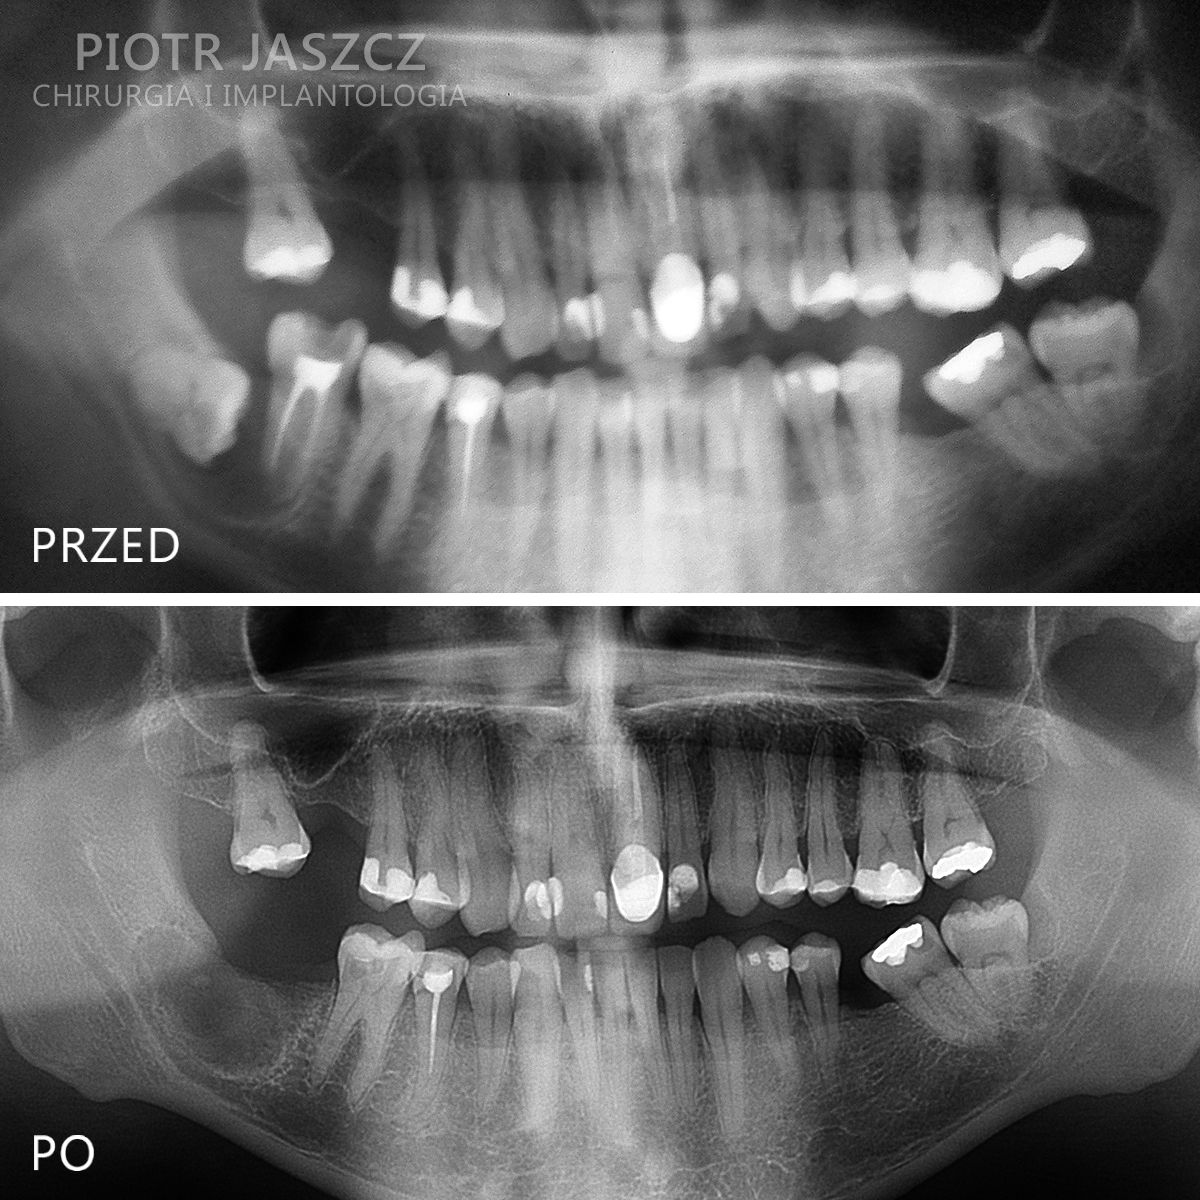

Specjalizuje się głównie w skomplikowanych odbudowach implantologicznych pacjentów bezzębnych oraz w zaawansowanych regeneracjach kostnych w leczeniu implantologicznym metodami przeszczepów kości własnej, jak również w przeszczepach tkanek miękkich w celu regeneracji dziąsła przy zębach lub przy implantach.

Wykonuje zabiegi odtworzenia zębów w 24h, polegające na usunięciu wszystkich zębów w szczęce lub żuchwie, wszczepieniu implantów metodą All-on-4 lub All-on-6 oraz oddaniu mostów na wszczepionych implantach w 24h. Metamorfozy szczęki w 24h.